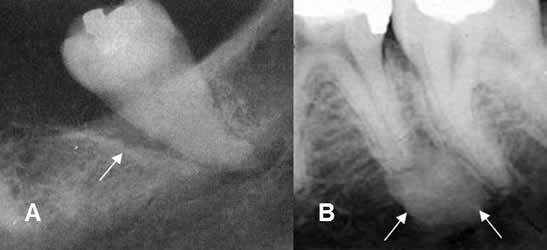

Fig 51 B. Osteitis periapical.

A y B: Rx periapical. Aumento del espacio periapical, por enfermedad periodontal. Los bordes son escleróticos, por evolución crónica. En B se aprecia aumento de la densidad en la cresta alveolar, por osteitis esclerosante.